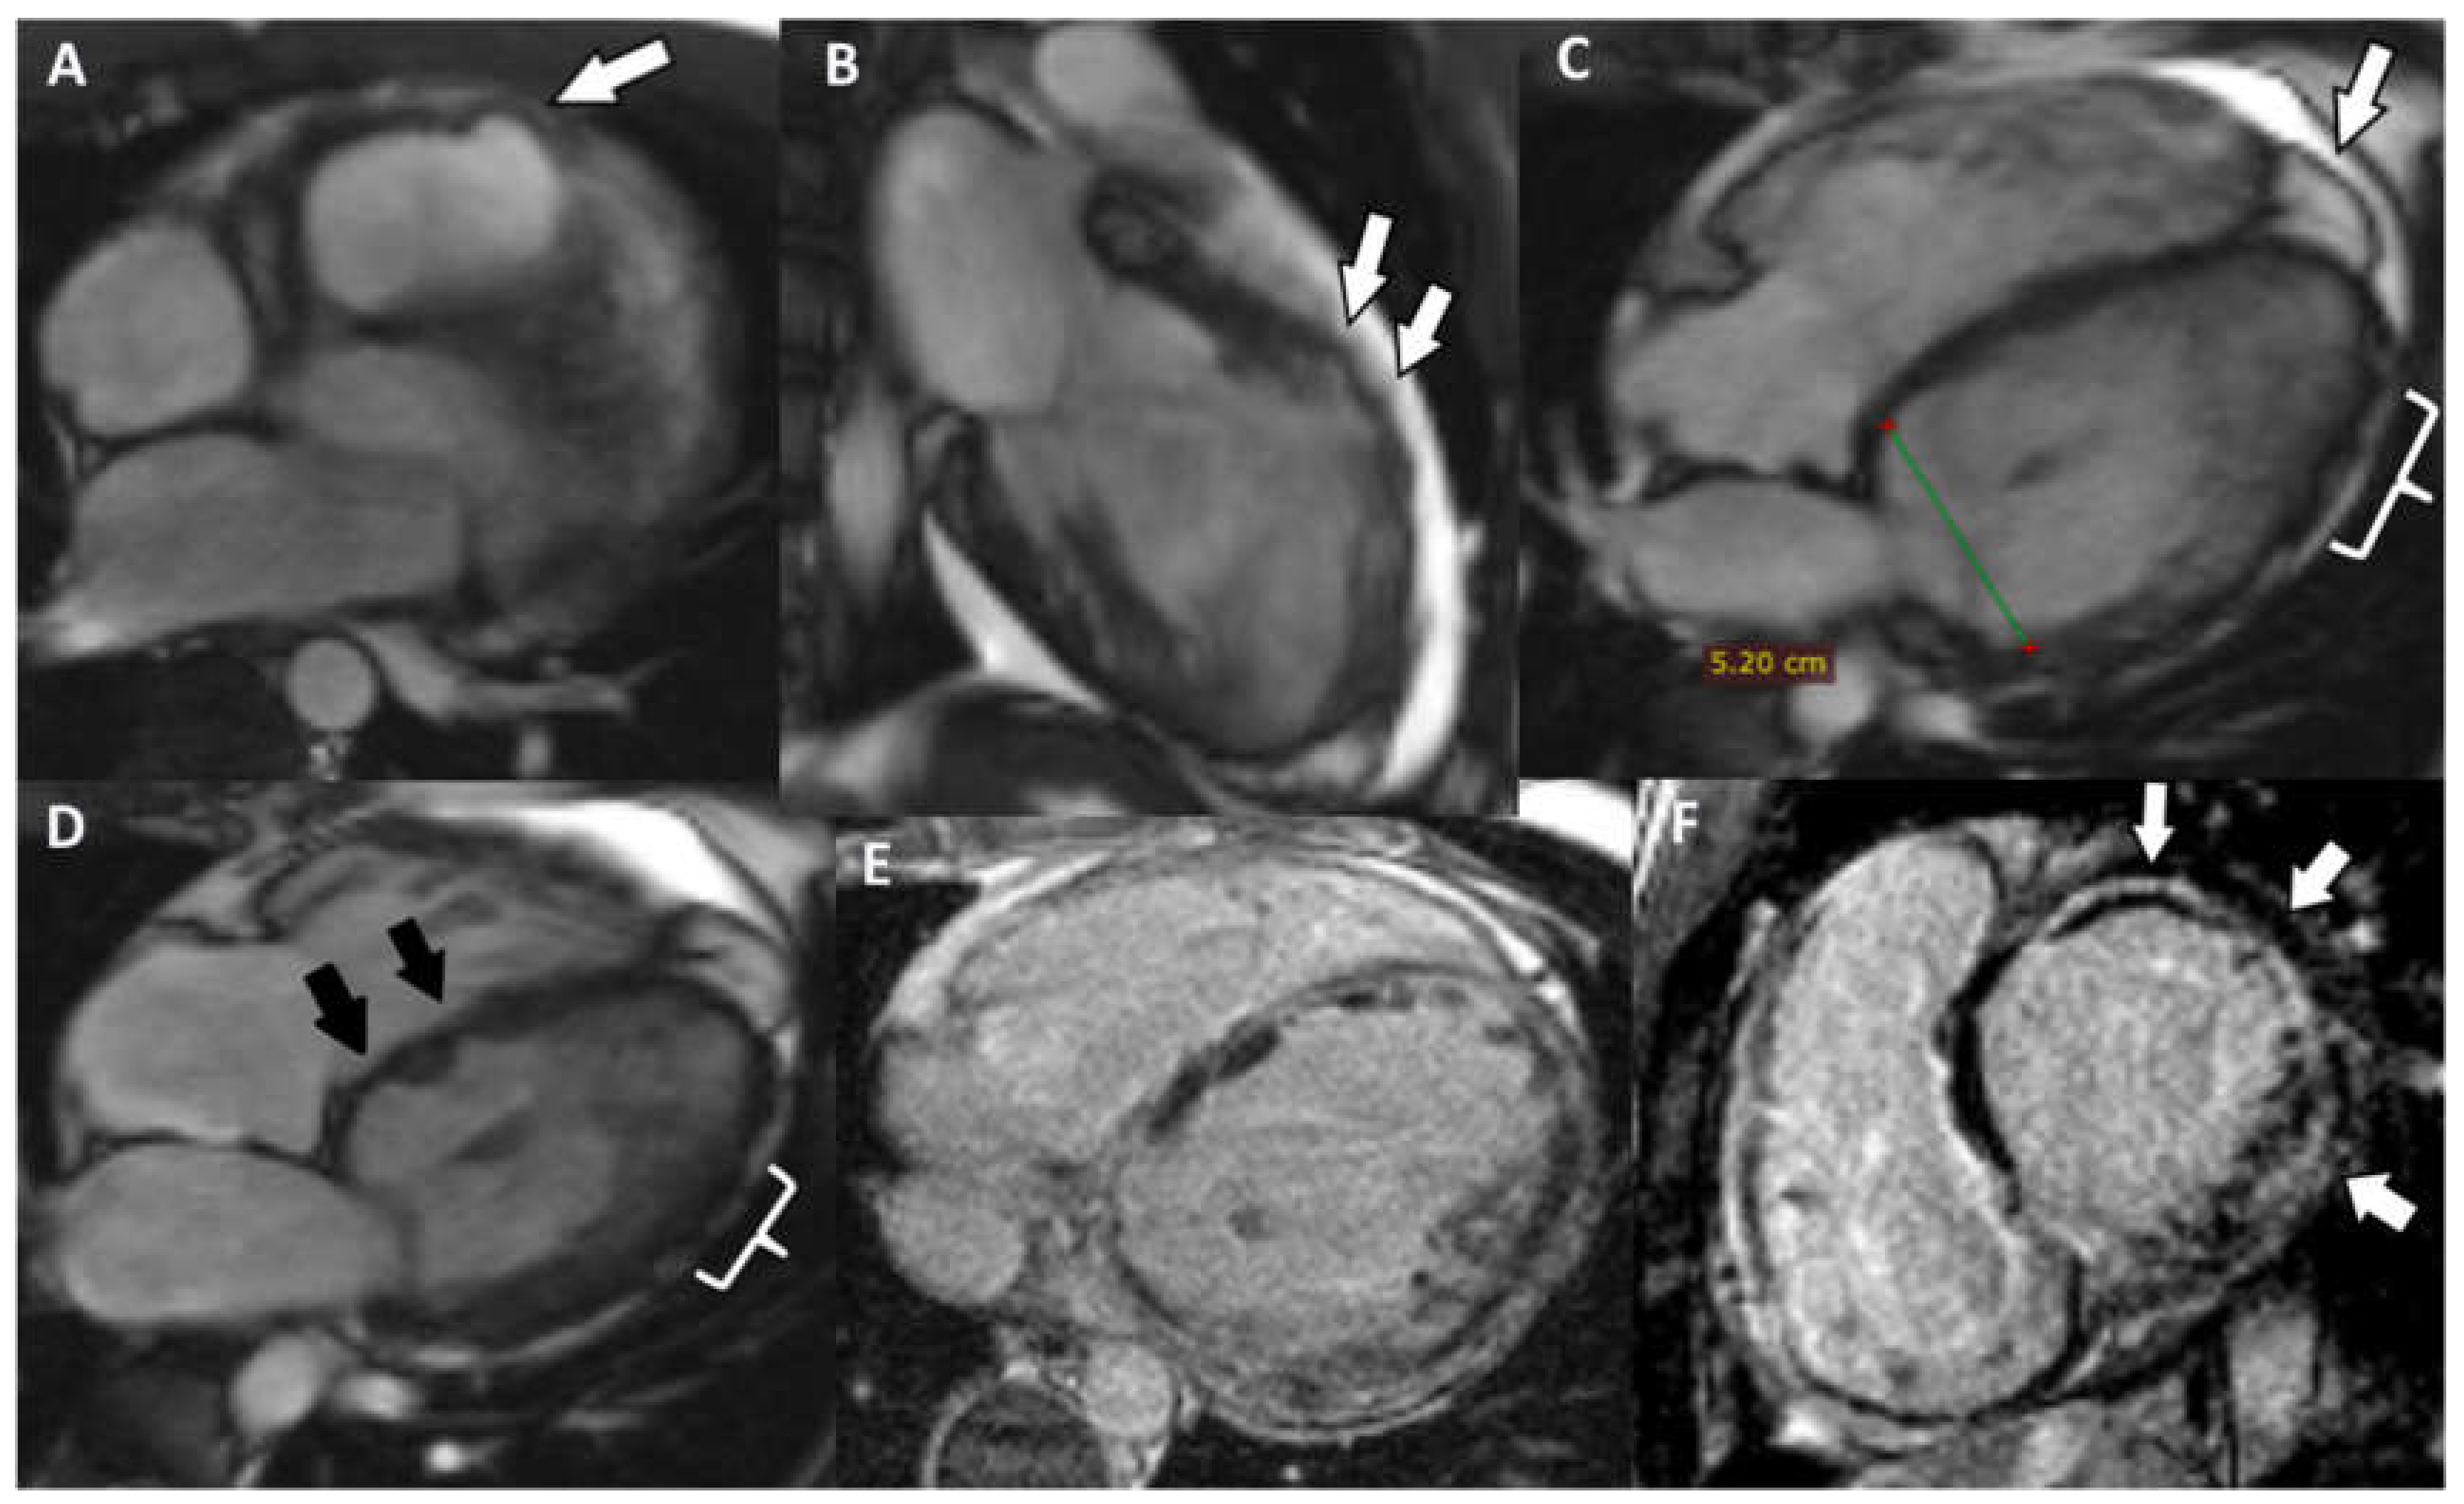

A cardiac MRI showed the following: dilated LV (51/60 mm), non-dilated RV (41 mm short axis) (Figure 6A), global hypokinesia of the LV and RV, more severe at the level of IVS, without dyskinetic areas. The pattern of the LGE revealed inhomogeneous midmyocardial fibrosis of all the walls of the LV in the basal, mid and apical segments, with scattered area of normal parenchyma (Figure 6B,C). The ventricular function is severely altered (LVEF = 23%; RVEF = 25%; EDV/S = 72 mL/m2).

Figure 6. (A) Short axis Cine-GRE sequence: basal dilatation of the LV, normal size RV; (B) short axis delayed postcontrast PSIR sequence: concentric midmyocardial LGE of LV; (C) LV two chambers delayed postcontrast PSIR sequence: non-uniform midmyocardial LGE of the anterior wall of the LV.